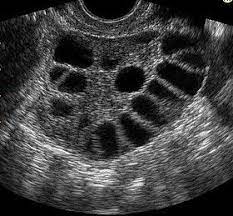

The PCOS ultrasound image dataset was collected from Kaggle [39]. The data folder consists of ’train’ and ’test’ subfolders, each containing two categories: ’infected’ and ’notinfected’. The infected folder contains images of ovaries with PCOS, while the notinfected folder contains images of healthy ovaries. In the train directory, the infected folder contains 781 images, and the notinfected folder contains 1,143 images. The test directory includes 787 infected images and 1,145 noninfected images. Figure 2 illustrates ultrasound scans of both infected and noninfected ovaries. Visual differences between infected and noninfected ovaries are apparent. In Figure 2(a), the ultrasound image shows characteristic holes (follicles), which distinguish it from Figure 2(b) (noninfected), where no such holes are present.

(a) Infected Ultrasound Image

(b) Noninfected Ultrasound Image

Figure 2: PCOS infected and noninfected ultrasound images